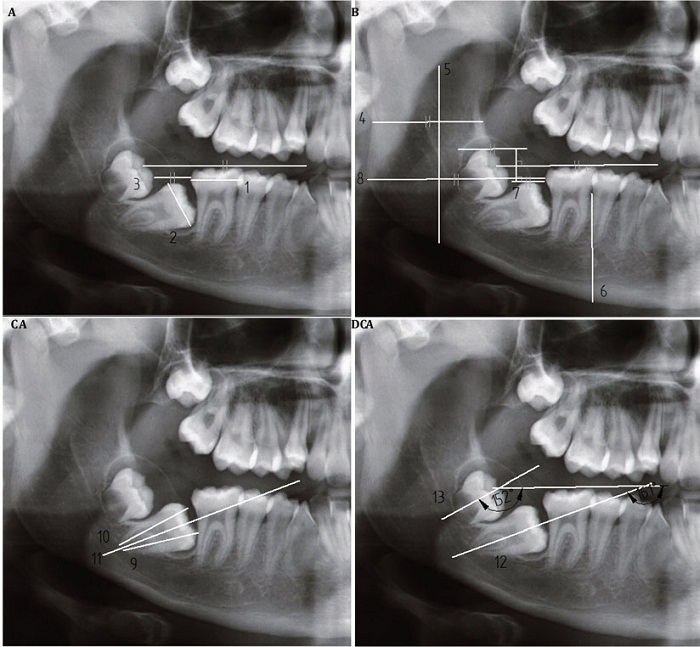

Toma y análisis de medidas angulares y lineales: para identificar los parámetros dentoesqueléticos lineales y angulares que caracterizan el sitio de impactación, unilateral o bilateral, se utilizaron las 13 medidas reportadas por de Shapira y colaboradores, en 2011. En la tabla 1 se encuentran definidas cada una de estas medidas, y en la figura 1 se observan las mediciones realizadas en una radiografía panorámica. Se seleccionaron pacientes de 11 a 15 años de edad para comparar las medidas del lado de impactación unilateral con respecto al no impactado. Se evaluó la variabilidad intrasujeto y se utilizó el coeficiente de correlación intraclase (CCI), con valores superiores al 80 % en todas las mediciones realizadas en el programa Siemens PLM Software SOLID EDGE ST8®. Los datos se consignaron en una base de datos en Microsoft Excel® para la cuantificación final y se analizaron en el programa IBM SPP6 Statistics®, versión 23. Estadística descriptiva y la prueba T de Student se utilizaron para comparar las medidas lineales y angulares. Error alfa: p < 0,05.

Radiografía panorámica de un paciente con impactación bilateral de 2MM, donde solo se muestra el lado derecho. A) Medidas lineales 1 a 3. B) Medidas lineales 4 a 8. C) Medidas lineales 9 a 11 D) Medidas angulares 12 y 13. Estas medidas están definidas en la tabla 1.